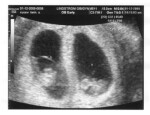

Dr.Jess called and wanted me to get an ultrasound to make sure the baby is okay. Its been 3 weeks since we found out we were pregnate and 3 weeks along. Now im 6 weeks and im feeling better. I told caleb i needed to go to the doctors and we went in his car to the hospital. DR.jess told me to lay down and relax , we will be able to hear the babys heart beat. The doctor was a bit concerned because my stomach wasnt growing so she wanted tocheck if everything was okay.

When dr.jess looked at the ultrasound it was as if she had seen a ghost , I was horrified I heard the heart beat but it was a very stange sound it was fast then low. " Well it looks like ur going to be expecting twins"- Dr.jess " What???" - mara I started to look at caleb as he looked at me . this is to much i just got over the fact that im not only having one baby but two. I can't beleive this i should have been more carefull. I ran out of the office and went on with life.